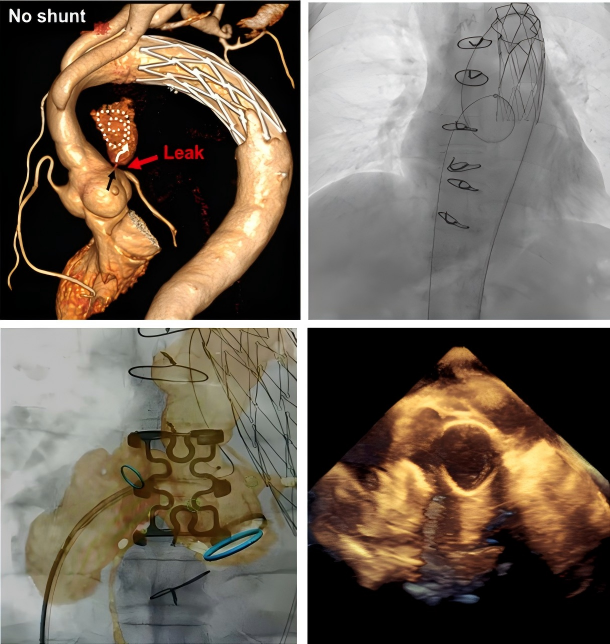

图说:

患者,男,61岁,升主动脉替换+全弓支架象鼻术后,窦管交界处吻合口漏

图A,B:主动脉CT三维重建从不同角度展示吻合口漏;

图C,D:主动脉CT和DSA显示吻合口漏与左冠状动脉关系和距离;

图E:术中封堵器释放前,复查造影,显示LCA开口显影良好;

图F:释放封堵器后复查造影,证实冠状动脉显影良好,不受封堵器伞盘影响;

图G:术后1个月复查主动脉CTA,提示封堵器位置良好,LCA显影良好;

图H:吻合口漏完全封闭,假性动脉瘤完全血栓化。

术前利用多种影像学方法评估吻合口漏,制定手术方案

术中DSA、超声、图像融合等多种方法引导完成介入治疗。